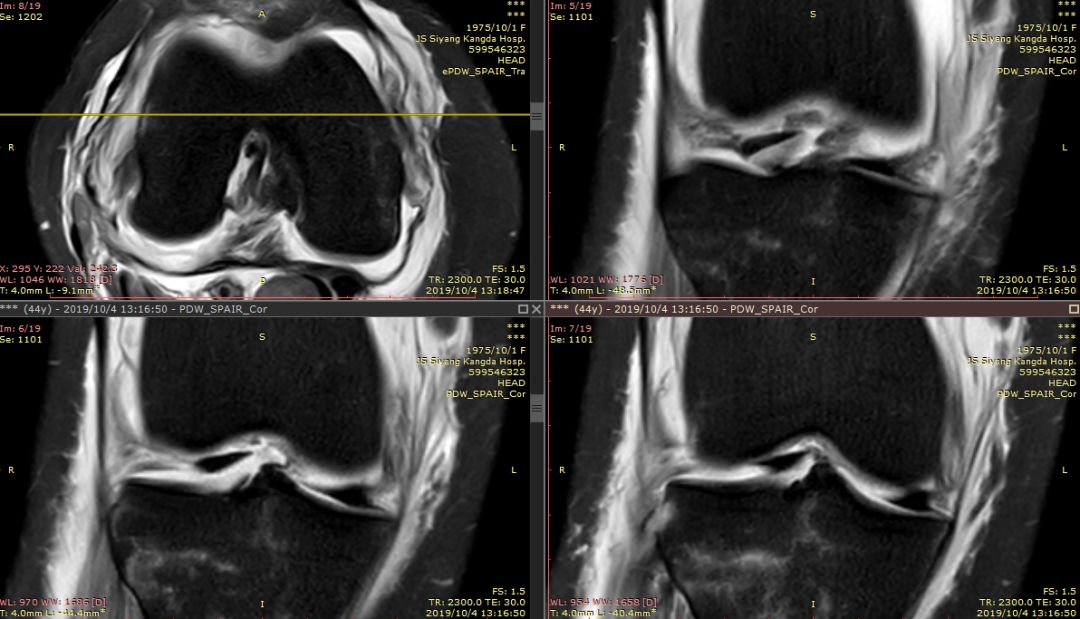

下图横断面的标线标记的是左下图,为外侧半月板的桶柄样撕裂移位

下图标记的是外侧半月板的撕裂